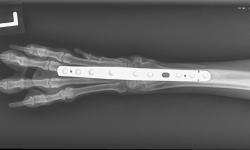

Pacient č.: 2. - rtg před operaci, hypertenze karpu.

pacient-2-3-pouzity-implantat-fixin-intrauma.